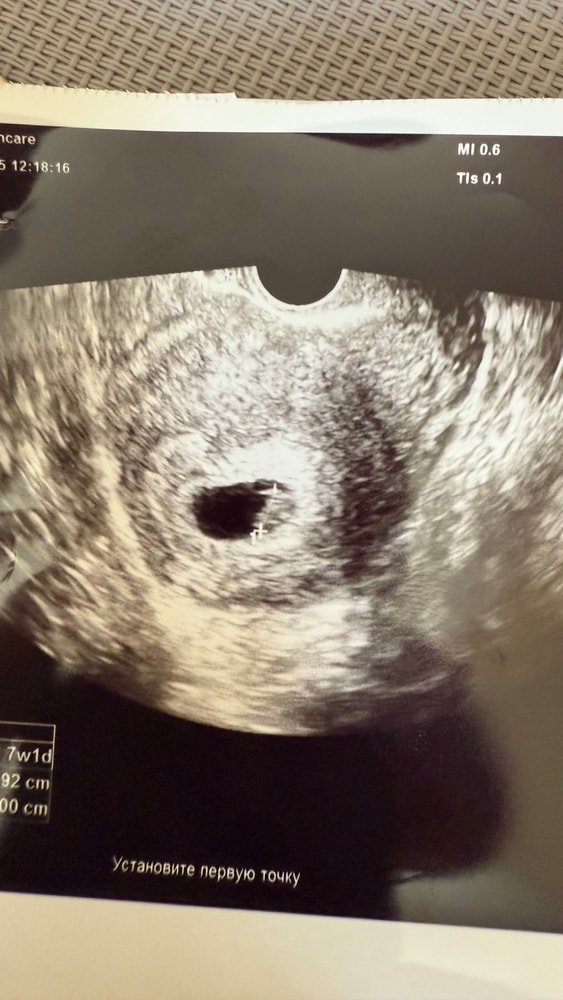

Узи 30 ДПП НЕ ОДНО ТАК ДРУГОЕ

Результаты УЗИПривет, сегодня сходила на узи , уже в другую клинику , напомню , на 26ДПП ПЯ 21.6 , ЖМ 6.1 , ЧСС 120 КТР замерить не смогли , эмбрион был за ЖМ ,

сегодня на УЗИ ПЯ 19,2 (уменьшилось ???)

КТР 8,9 (Слава Богу соответствует сроку 7 недель)

ЧСС 120

Напугала тем, что ПЯ какое то внутри неоднородное , с частично сетчатым внутренним содержимым !!! ЖМ вообще не визуализируется !!!!! Сказала что возможно патология и будет ЗБ 😭